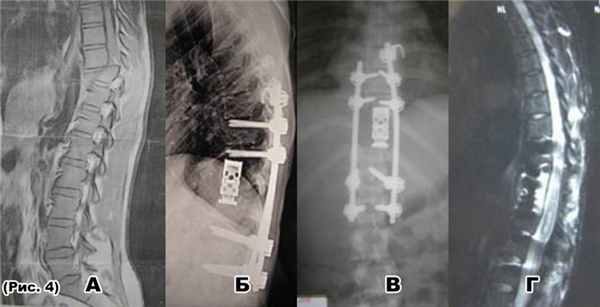

а) МРТ-переломовывихTh10 позвонка (стеноз п. к. 100%)

Декомпрессивно-стабилизирущие операции при неудачных операциях на позвоночнике

а) перелом стержней транспедикулярного фиксатора после неудачной операции на позвоночнике по поводу ПСМТ: переломовывихTh12 и компрессионно-оскольчатого переломаL1 позвонка;

б) на МРТотсутствует костный блок между Th11 и L1 позвонком, сохраняется стеноз позвоночного канала

в) и г)декомпрессивно-стабилизирующая операция: спондилодез аутотрансплантатами из ребраTh11-L2, гибридная фиксацияTh9-Th10-Th11-L2-L3 позвонков

д) на МРТ через 1-год после операции сформирован костный блок между Th11- L1 позвонками, стеноза позвоночного канала не определяется.